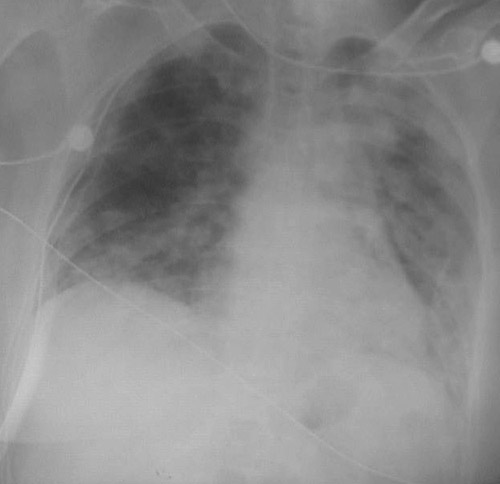

This chest radiograph demonstrates a worsening of the fluffy infiltrates in all lung fields as a consequence of pulmonary alveolar proteinosis.